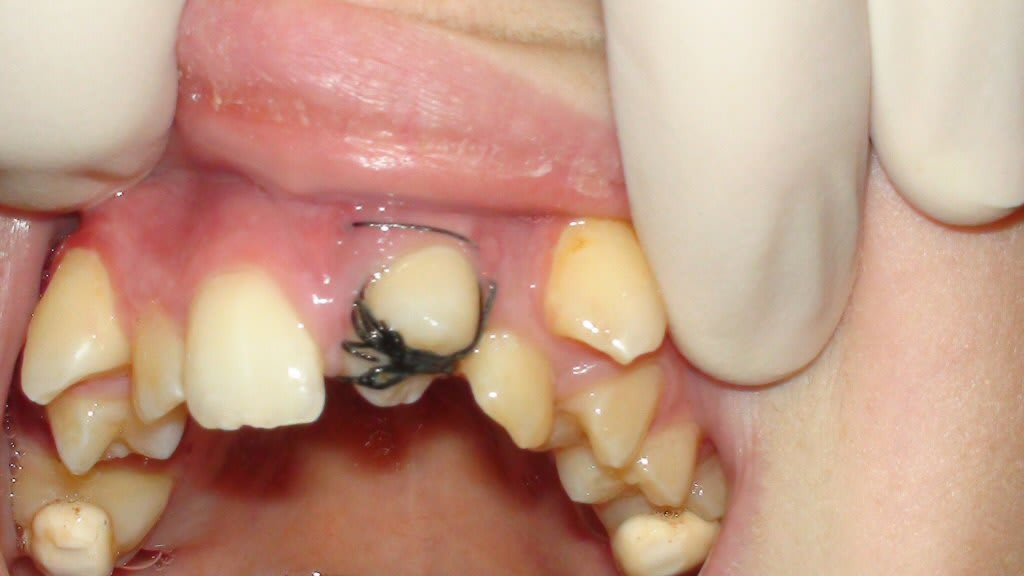

Comme ici ?

Mais la forme n'est quand même pas idéale, vous ne trouvez pas ?